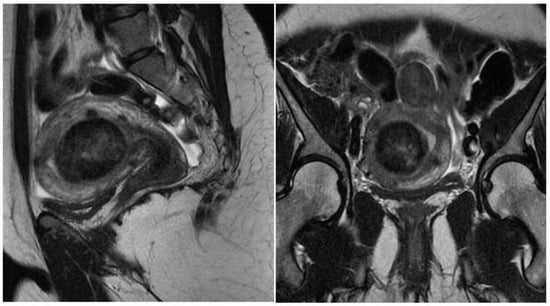

Myomectomy, whether laparotomic or laparoscopic, is a well-established procedure, widely performed with the goal of uterine preservation. In both approaches, the myomectomy technique is the same: incision of the serosa up to the pseudocapsule, identification of the myoma, traction and movement of the nodule, assistance in dissecting the plane of the pseudocapsule within the myometrium, and enucleation of the myoma from the uterine wall. This fibroid enucleation technique is known and performed by all gynecologists. When the pseudocapsule is reached, the chance of preserving the uterus will be greater, with less bleeding and less myometrial damage, which differs from adenomyosis resection, which does not have a pseudocapsule [21] (Figure 6).

Figure 6. Laparotomic and laparoscopic myomectomy preserving pseudocapsule.